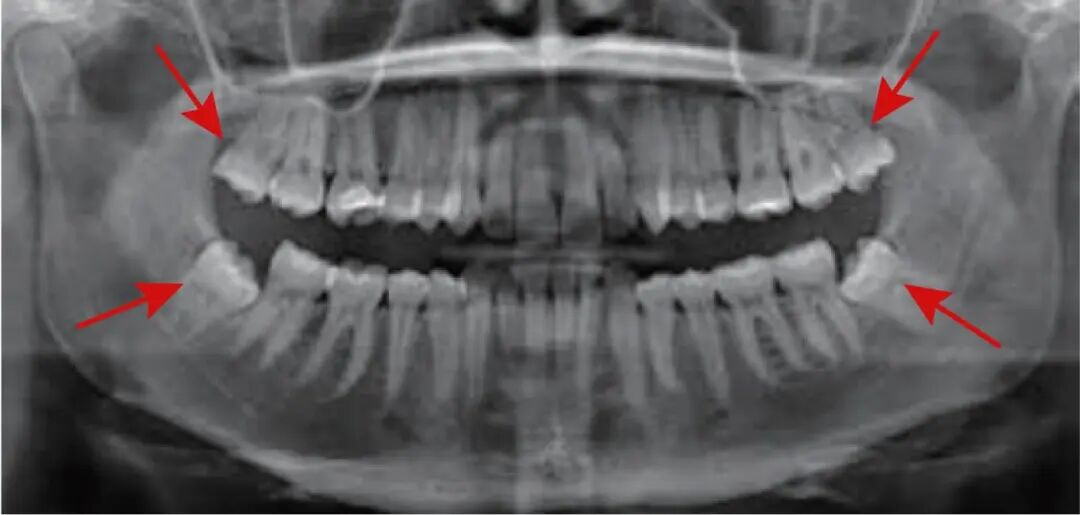

什么是智齿?

• 智齿又称“第三磨牙”,人类口腔中牙槽骨最后面的牙齿,从正中门牙往后数第8颗

• 数量为0-4颗。

• 萌出时间通常16-25岁,因萌出空间不足,不能完全萌出,通常又称阻生牙。